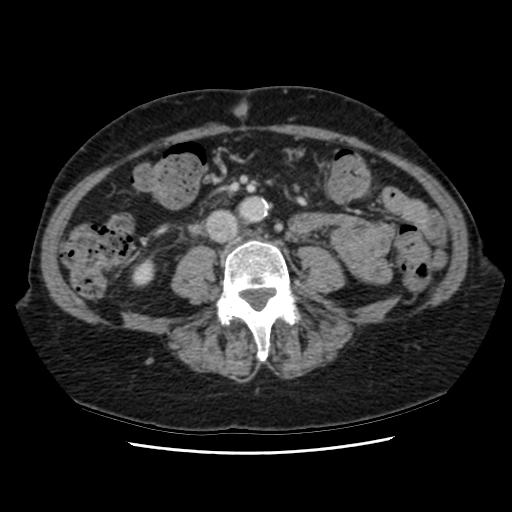

U cận hạch sau phúc mạc (Extra adrenal paraganglioma)

16/03/2026